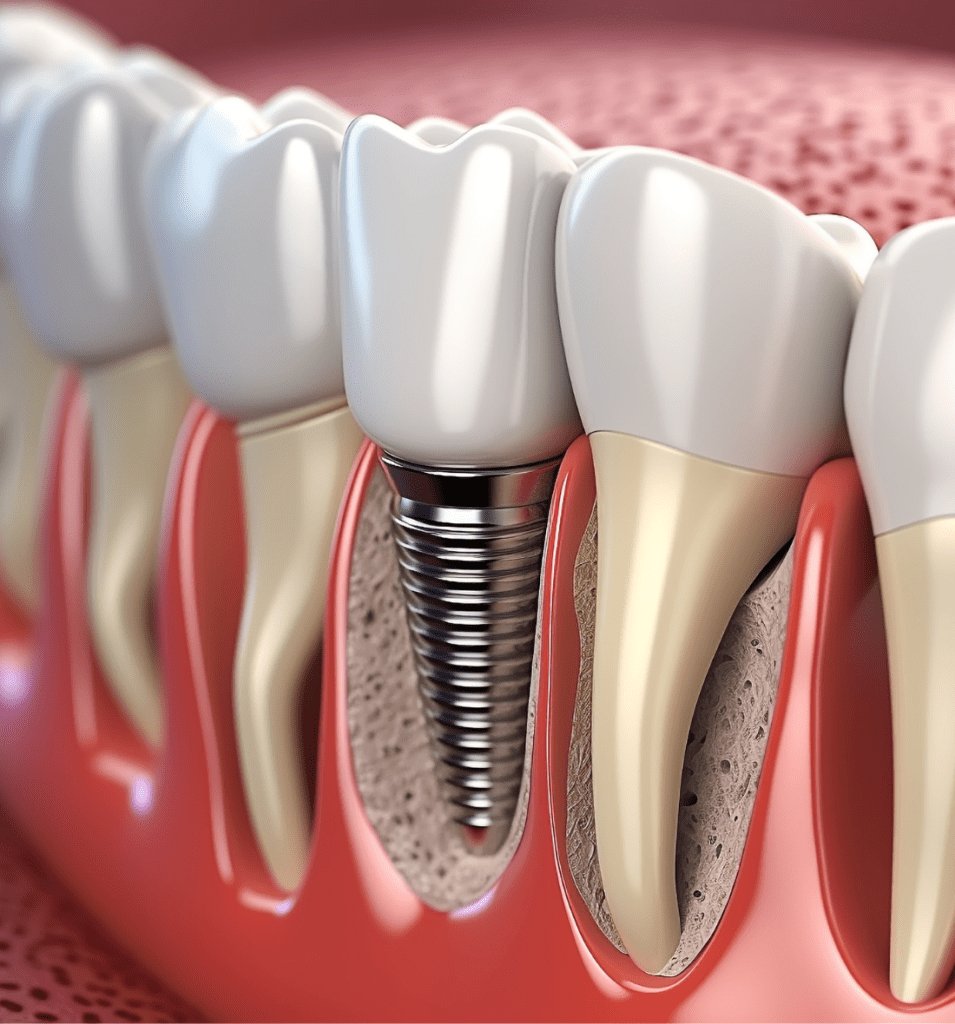

Restore Chewing Ability

Dental implants restore full chewing power, allowing you to enjoy meals without discomfort or restrictions.

Long Lasting

Dental implants are designed to be a durable, long-lasting choice, providing you with a reliable and permanent fix that keeps your smile beautiful for decades.